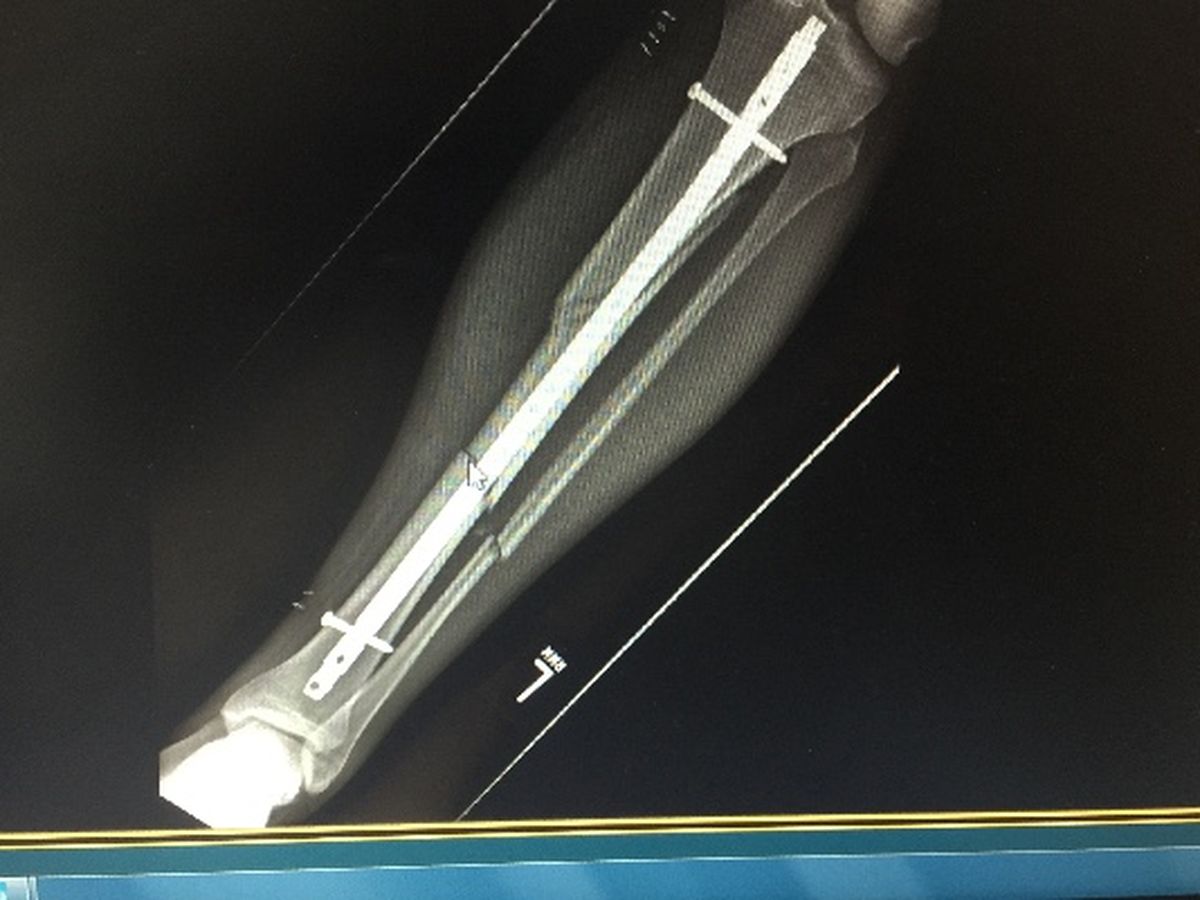

Adam was tragically injured while playing softball. It was a dirty play and a worse situation. Adam was in the hospital for eight days. He is the only income in a family of five. He is out of time at work and will be out of work for at least a couple months and possibly up to six months. While he is healing, his family has no means to survive. Adam works in public service, as both a corrections officer and a police officer for over ten years. He has done his job consistently, faithfully, and thanklessly. It's time for us to start protecting his family like he has ours for so many years. Anything helps.